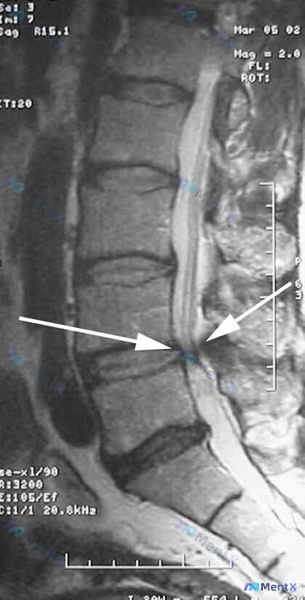

最近看到一个很有警示意义的病例,整理了一下思路和大家分享: 病例基本情况 - 患者:71岁女性 - 主诉:走路时臀部和腿部剧烈疼痛 - 诊疗经过:保守治疗无效,已计划行腰椎减压手术 - 影像:腰椎MRI(矢状位T2WI)提示L4-L5、L5-S1椎间盘脱水、突出/膨出,L4-L5节段硬膜囊前方明显受...